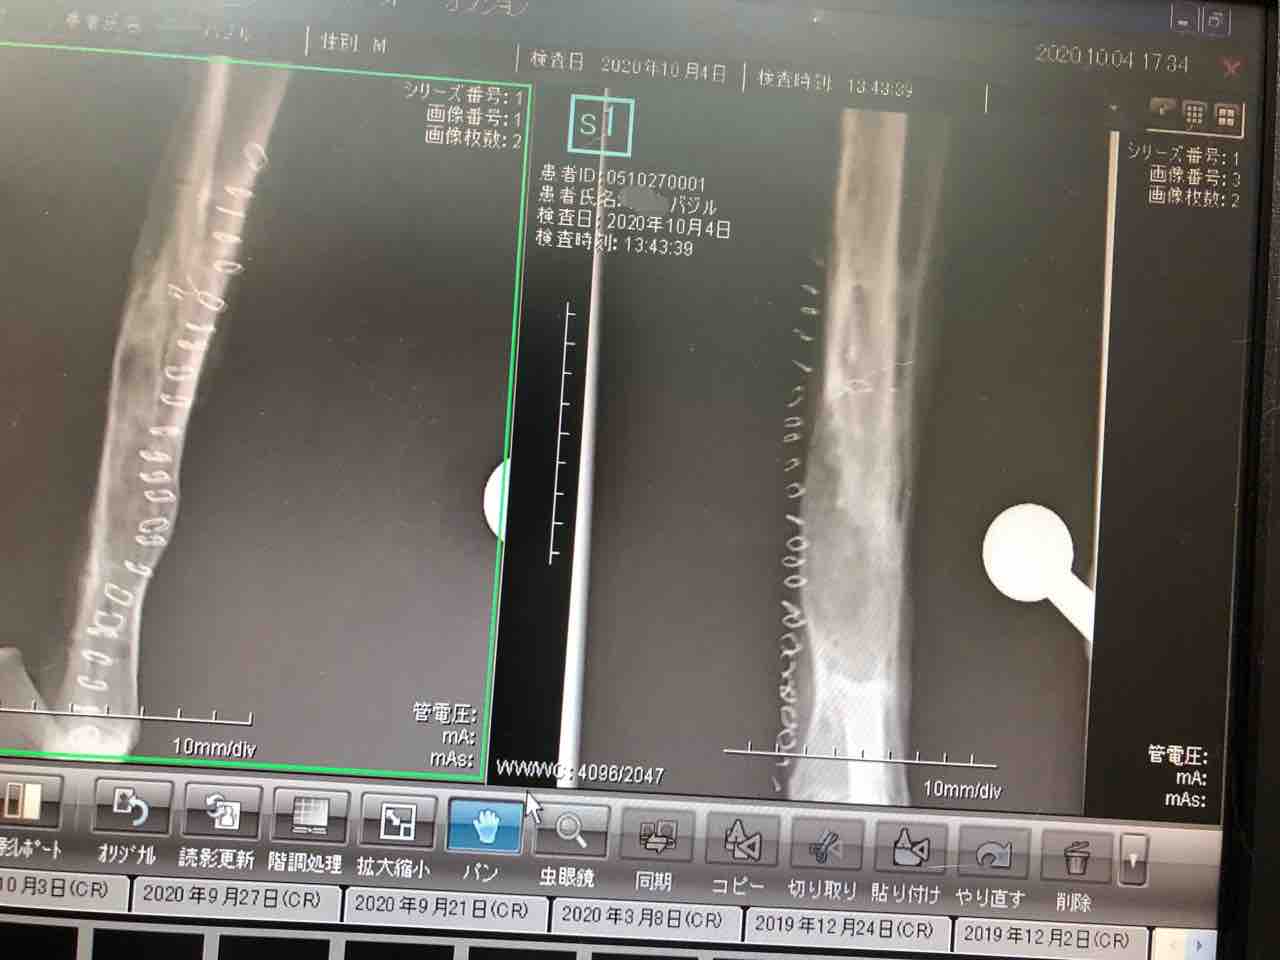

プレートを抜いた後のレントゲン写真

まだ骨がスカスカです

先生が見たところ、しっかりしてきている骨は今50%くらい...とのこと。

壊死し始めてるところもありました。

(最悪の場合、ダメになってしまうかも...とも)

今は絶対安静、毎日注射と消毒が必要で、後はプレートを抜いたことで回復するのを祈るしかないと